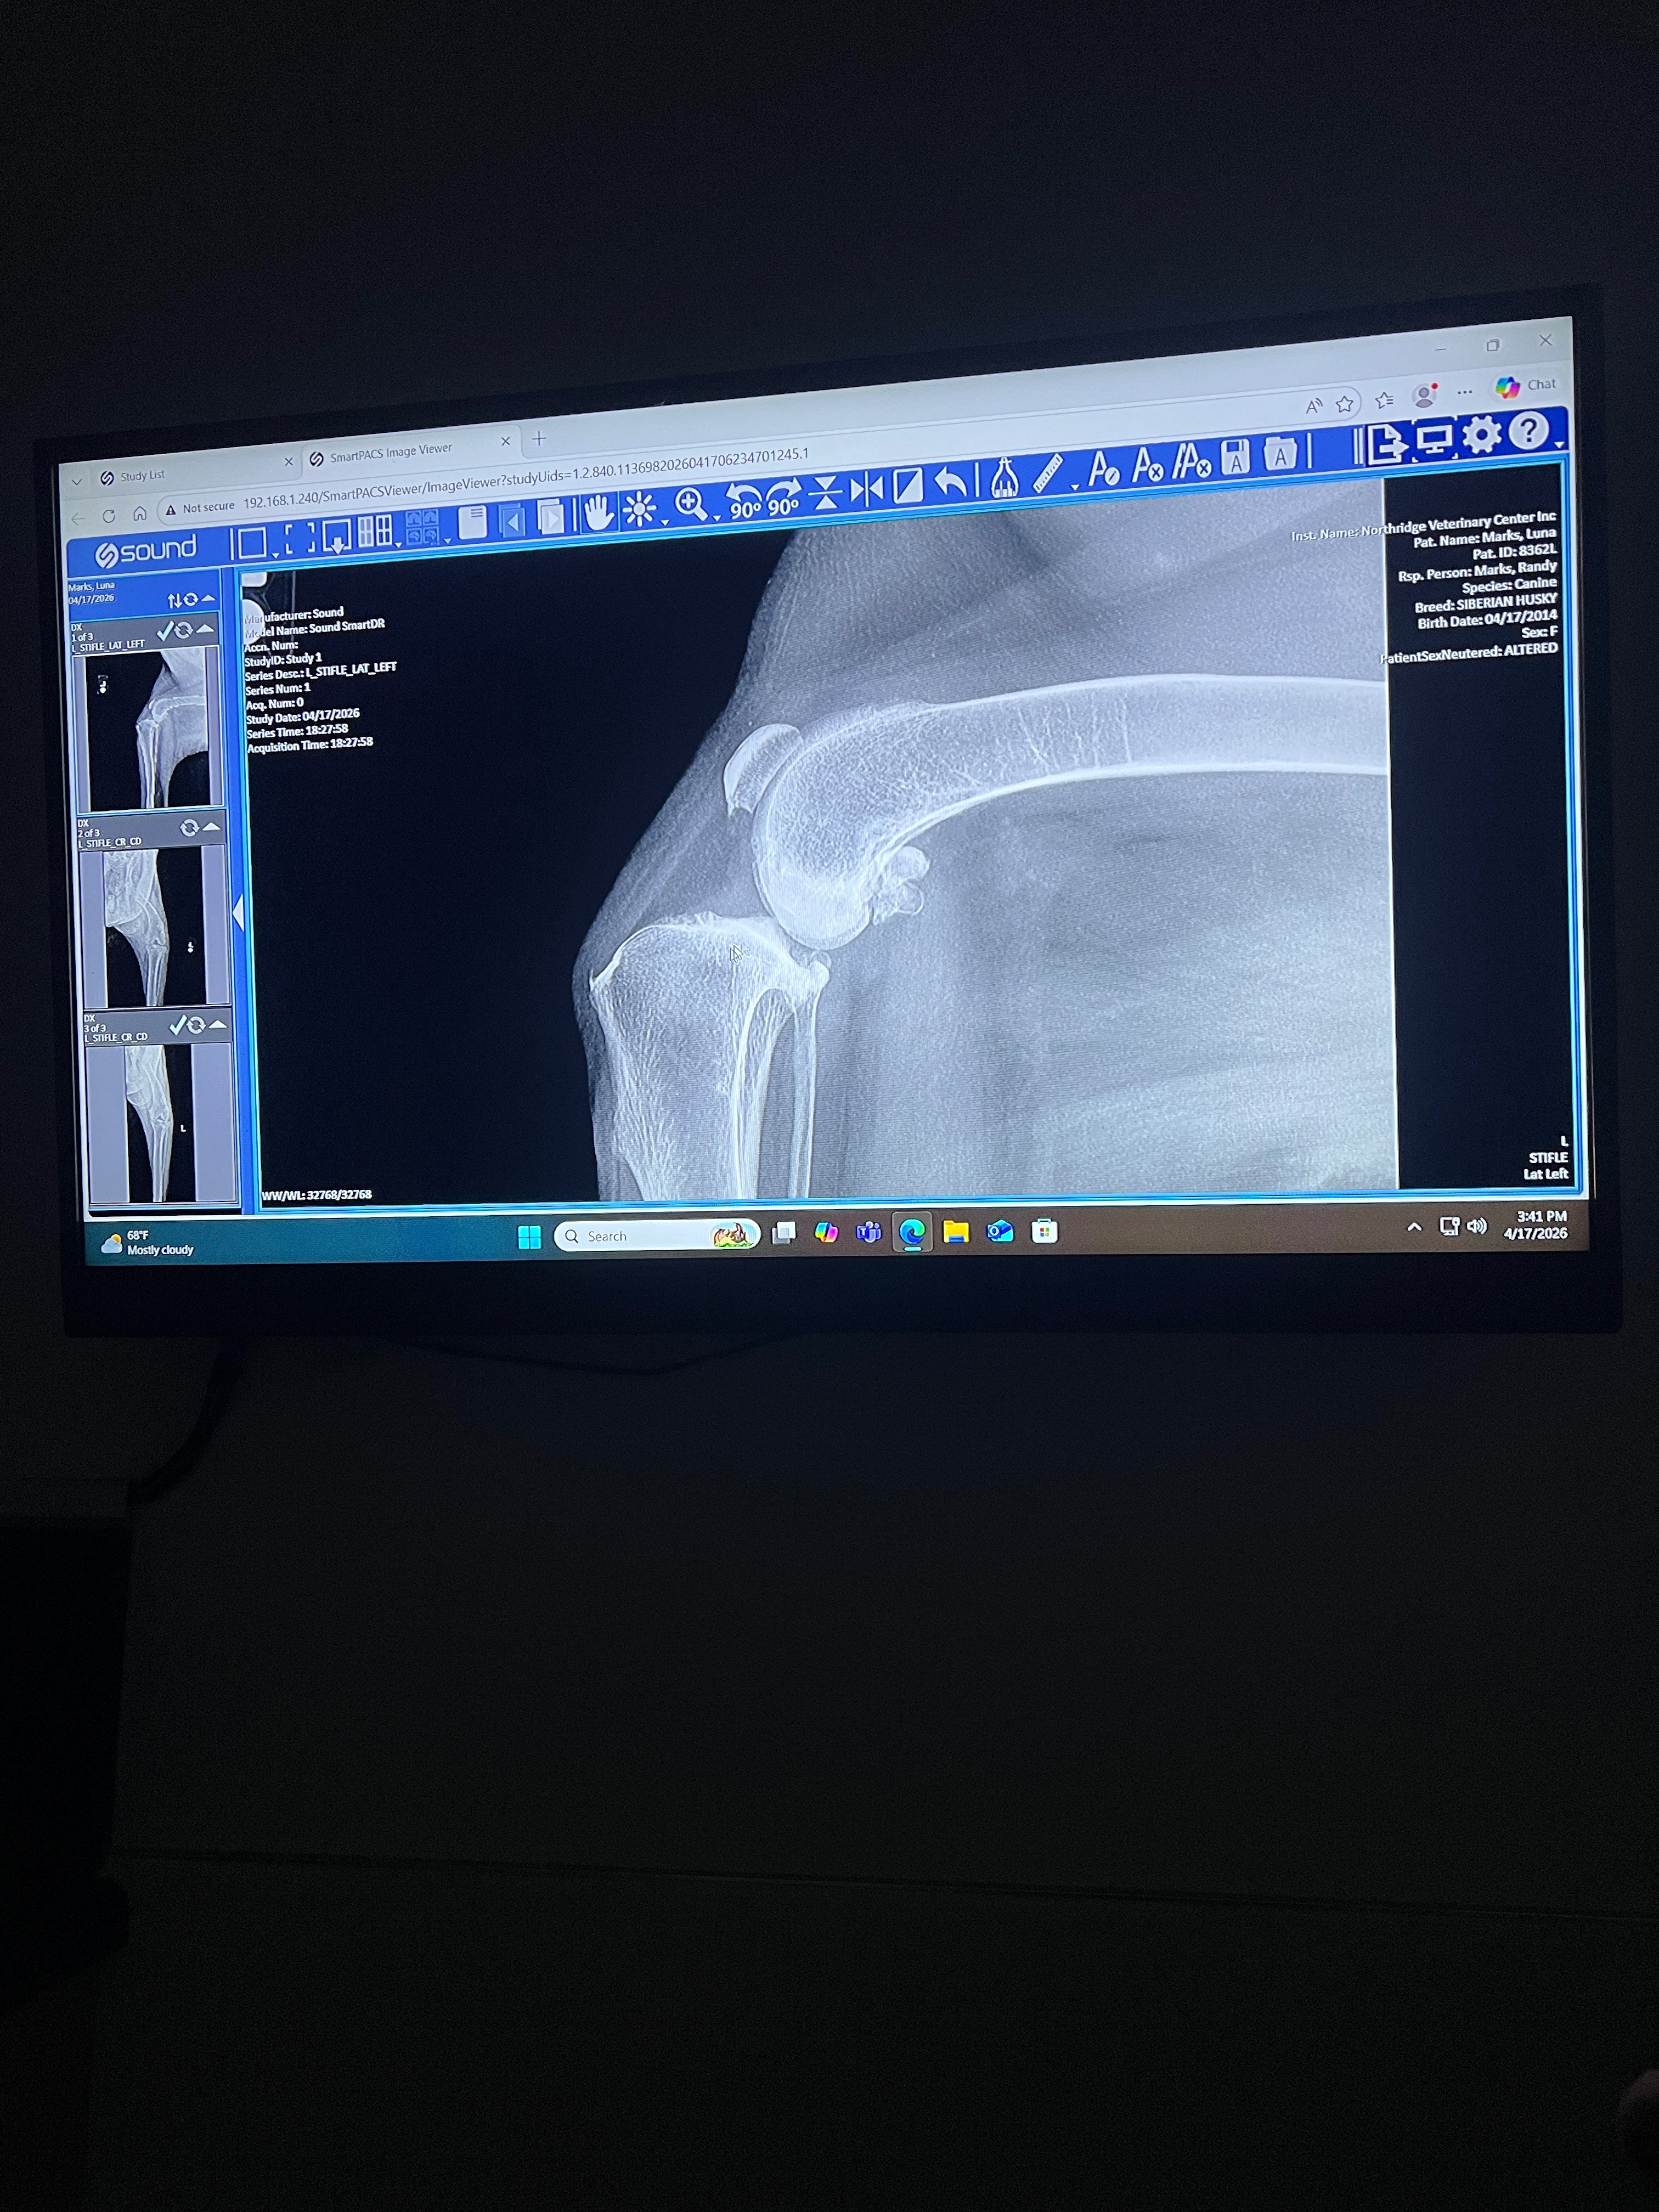

A couple days ago, Luna had an accident on a walk & tore the ligament in her knee. This is known as a cranial cruciate ligament rupture, or in laymen’s terms a dog’s torn ACL. Since then, she can barely put weight on her leg & is in a great deal of pain. After X-rays & an exam, the vet told me she needs TPLO surgery to fix it.

The part that gives me hope is that she’s still otherwise healthy. The vet said if everything goes well, she could have 2 to 3 more good years of quality life, possibly even more. Additionally, she has arthritis, which doesn’t help at her age & we want to get this taken care of as soon as possible to avoid her rupturing her other knee. The vet said this is very common without surgery. Luna still has a spark in her & I wholeheartedly believe it’s not her time to go.